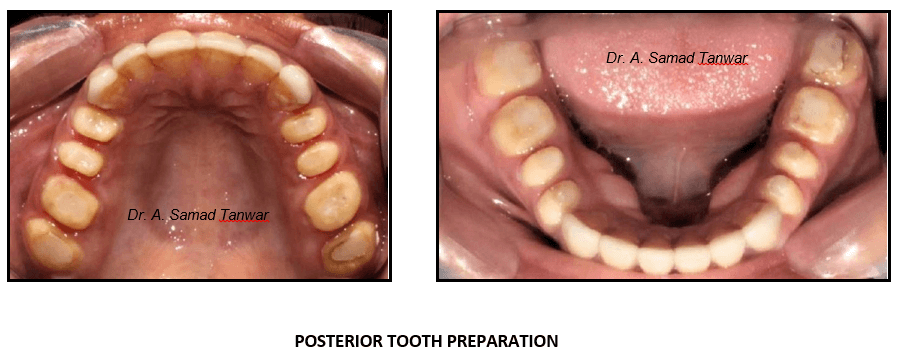

Posterior tooth preparations were completed to receive Porcelain fused to Metal restorations.

The preparation should be conservative which is the main principle governing the fabrication of ceramic

We start with the tooth preparation using the mock-up in place. Horizontal depth grooves were made using depth

The thickness of the ceramic laminate should be 3-0.5mm

A chamfer finish line is given and a bevel is given at the incisal edge to give a butt joint.

The preparation can be checked using

Gingival retraction was done using 000 knitted retraction cord